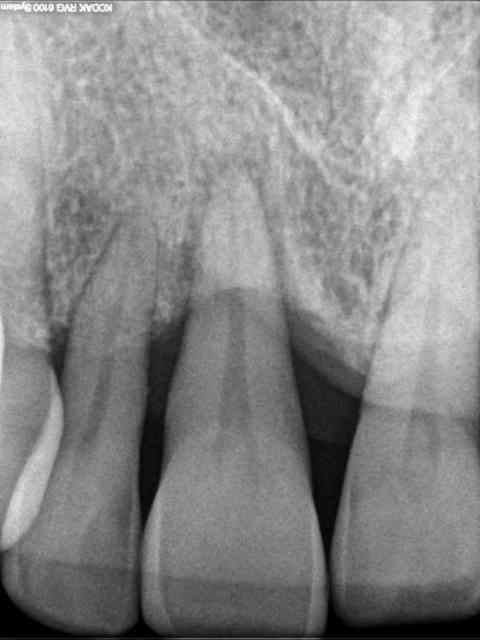

patiente 43 ans, très souriante, rigole tous le temps, fumeuse devant l'Eternel (1paquet/jour).

la parodontite et la mobilité sur 12 l'inquiète d'autan plus que les dents sont de plus en plus mobiles.

la 12 est perdue, mais également la 11 qui subit déjà une forte résorption gingivale.

21 et 22 pas beaucoup mieux.